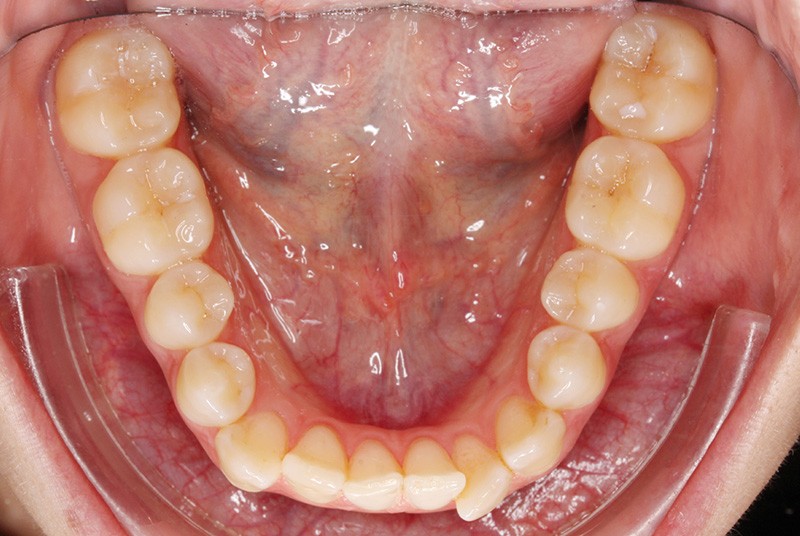

Elle présente une classe I dentaire en denture adulte. Son sourire est perturbé, notamment par la microdontie de son incisive latérale maxillaire droite (la 12). On constate un encombrement modéré au maxillaire (bimarginotopie mésio-palatine et disto-vestibulaire de 13) et plus marqué à la mandibule (monomarginotopie mésio-vestibulaire de 32 et de 43) (fig. 1-6).

Les milieux inter-incisifs ne sont pas coordonnés, à torts partagés, avec une légère déviation à droite du milieu inter-incisif maxillaire et une déviation plus marquée à gauche du milieu inter-incisif mandibulaire ainsi que du point menton. 32 et 33 présentent une tendance à l’exoclusion.